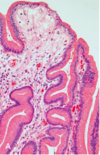

Which characteristics of this image are distinguishing features of H. pylori gastritis?

- Lymphoid aggregates w/ germinal centers

- Abundant subepithelial plasma cells in superficial lamina propria